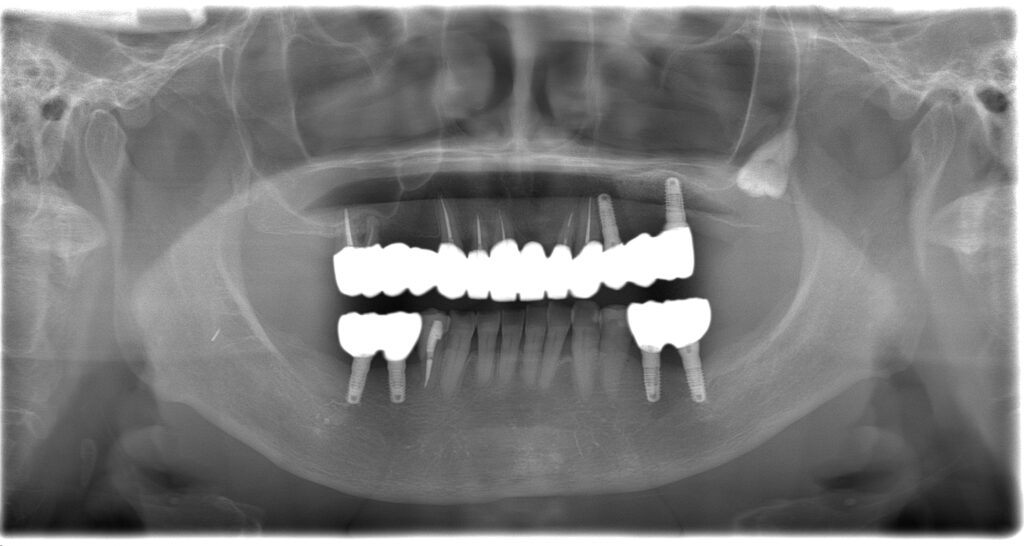

BEFORE

主訴

全体的に見た目を綺麗にしたい。奥歯でしっかり噛みたい。

診断名・主な症状

臼歯部欠損

年齢

65歳

治療内容

インプラント埋入(左下5・6,右下5・6,左上4・6)

サイナスリフト(左上4・6)

ジルコニアBr(右上6−左上3)

E –MAX CAD(右下4)

セラミックインレー(左下4)

治療期間/

通院回数

約1.5年/約20回

費用

インプラント治療 約2,000,000円

その他被せ物治療など 約1,000,000円

合計 約3,000,000円

*いずれも税込